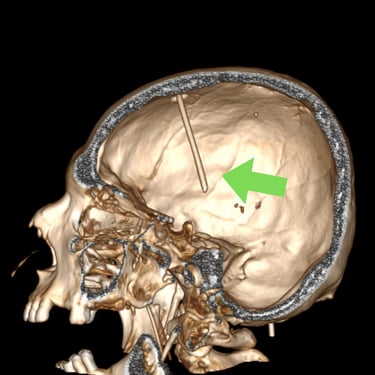

Hidrocefalia – Colocación de derivación ventriculoperitoneal (DVP).

La hidrocefalia es una condición neurológica causada por la acumulación anormal de líquido cefalorraquídeo dentro de los ventrículos cerebrales, lo que genera aumento de la presión intracraneal y deterioro neurológico progresivo. La colocación de una derivación ventrículoperitoneal (DVP) es el tratamiento quirúrgico más utilizado para controlar esta patología. Este sistema permite drenar el exceso de líquido desde el cerebro hacia la cavidad abdominal, donde se reabsorbe de manera segura. La intervención oportuna alivia los síntomas, previene daño cerebral y mejora la calidad de vida del paciente.